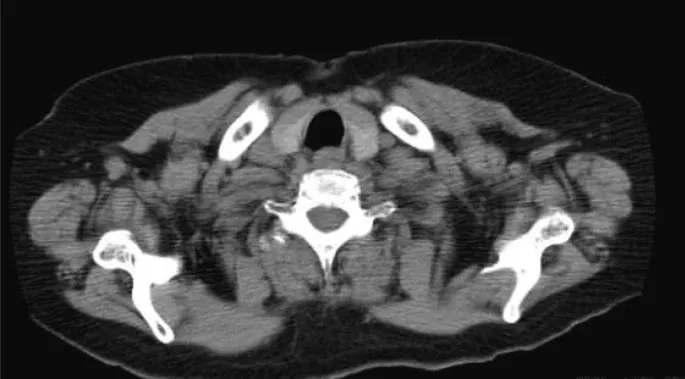

CT及超声检查均未见异常(图3)。经与本院内分泌外科会诊,2个月行超声引导下细针穿刺活检2次;但在甲状腺中未检测到癌成分。一般来说,隐匿性甲状腺癌的颈部淋巴结转移病例需要全甲状腺切除术。然而,考虑到本例患者PTC进展缓慢、患者年龄、既往有慢性心功能不全、高血压、糖尿病、哮喘病史及整体身体状况,内分泌外科医生未能获得患者的知情同意;因此,对该患者选择密切观察随访。手术后8年,未见颈部肿瘤复发或甲状腺癌大小变化,患者进展良好。

图3. CT结果